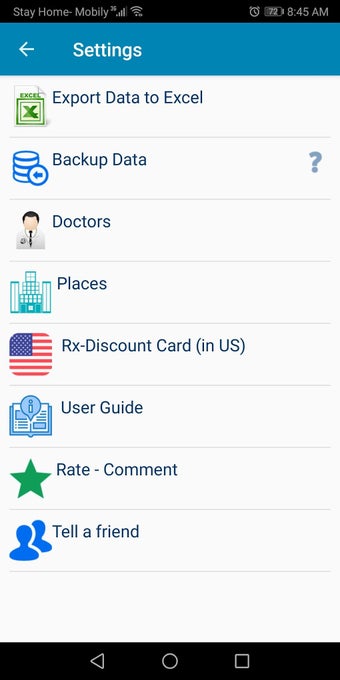

The Android Medical Records App by MedClin is a free medical records tracker app that allows users to store anamnesis, patient records, patient history, and health information. It is easy to use and provides numerous features such as username and password authentication, exporting medical data to Excel Sheet, and the ability to attach medical documents of any type. The app also has a smart search feature that allows users to search for patient information by name or ID, and even capture a photo for their profile.

In addition, the app has a blood pressure module that measures systolic, diastolic, and pulse, and allows users to export blood pressure reports to either PDF or graphs. The app also has a blood glucose (sugar) module that records blood sugar values and allows users to export blood glucose reports to either PDF or graphs. Users can also send blood pressure and blood sugar reports to their doctor. The app is compatible with multiple screens, including phones and tablets, and works on Chromebook systems. Overall, the Android Medical Records App is a great tool for patients and physicians alike for managing patient information and medical records.